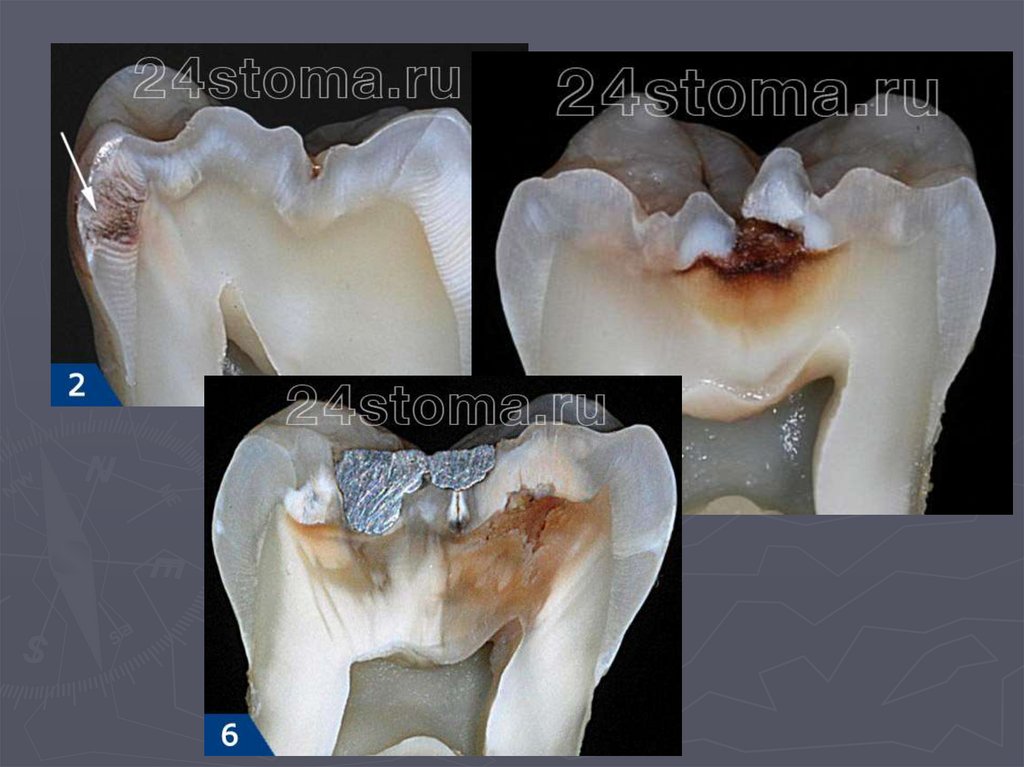

49. Глубокий кариес

► во временных и постоянных зубах с

несформированными корнями практически не

диагностируется.

Клинически глубокий кариес:

► наблюдается в постоянных зубах со сформированными

корнями;

► боли от механических ,химических, температурных

раздражителей;

► после устранения причины боль исчезает;

► кариозная полость значительных размеров;

► дентин размягченный, пигментированный;

► зондирование болезненно по дну.

38. КЛИНИЧЕСКАЯ КАРТИНА СРЕДНЕГО КАРИЕСА при декомпенсированной форме:

► при локализации кариозной полости в фиссурах

определяется небольшое входное отверстие;

► при раскрытии обнаруживается кариозная

полость с податливым дентином;

► края кариозной полости нависают;

► эмаль тонкая, хрупкая;

► дентин светлый, влажный, размягченный, легко

удаляется экскаватором;

► зондирование болезненно по

эмалево-дентинному соединению.